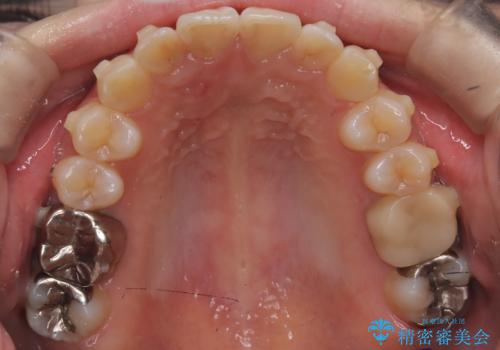

前歯のガタつきをマウスピース矯正で改善

- 前歯のガタツキが気になると来院されました。

奥歯の噛み合わせは綺麗に噛んでいたため、前歯の叢生(でこぼこ)に集中して治療するように計画しました。